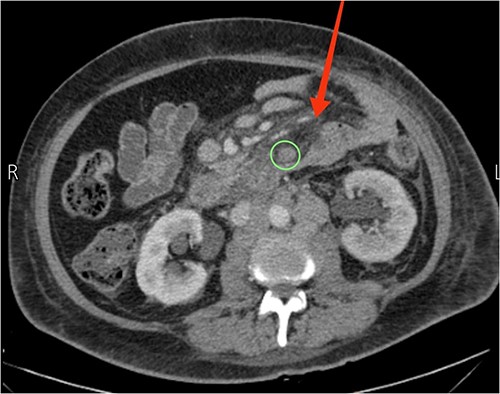

Upon examination, she had normal vital signs. Abdominal examination revealed a mildly distended and generally soft abdomen with tenderness in the upper quadrants. Bowel sounds were reduced. Lab tests showed a significantly elevated C-reactive protein level of 265 mg/dL (normal range: <0.3 mg/dL). Axial CT scan revealed mesenteric edema, jejunal wall thickening, surrounding fat stranding, and an enlarged mesenteric lymph node (Fig. 2). An emergent diagnostic laparoscopy revealed a mildly dilated viable jejunal loop, ~16 cm in length, located 10-cm distal to the ligament of Treitz. Additionally, a milky jejunal mesentery and a moderate amount of chalky ascitic fluid in perihepatic, perisplenic, and pelvic regions were observed (Fig. 3). Fluid analysis confirmed chylous ascites with a triglyceride level of 320 mg/dL (normal range: <110 mg/dL). Histopathological analysis of an excisional biopsy revealed abnormally dilated lymph vessels, leading to a diagnosis of cavernous mesenteric lymphangioma with chylous ascites. Surgical excision was not pursued because of the patient’s aggressive metastatic CUP state. She had an uneventful postoperative course, discharged on the fourth day, and was referred for follow-up with the oncology team for palliative chemotherapy.

Axial view CT showing prominent mesenteric edema with jejunal wall thickening and surrounding fat stranding (arrow). An enlarged mesenteric lymph node can also be seen (circle).